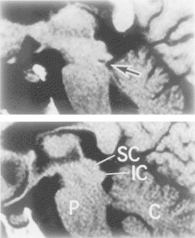

Damage of the inferior colliculi (top)

that resulted in "word deafness."

From Johkura et al. (1998)